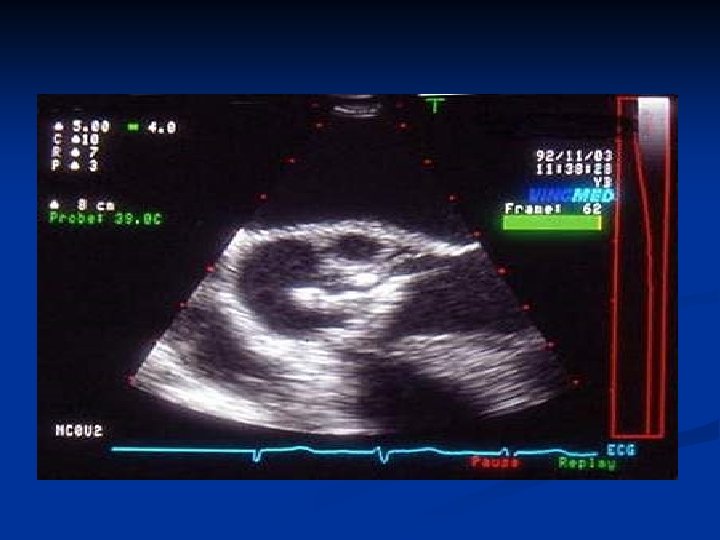

A l’arrivée dans le service… Hyperthermie (38° 6) , marbrures +++ , encombrement laryngé oligurie , ascite n TA : 14/4 n ETT : -volumineuse végétation aortique de 2 cm -fermeture prématurée de la valve mitrale -fluttering de la valve aortique -FE à 40% -épanchements pericardique et pleuraux. n Bilan d’extension : TDM cérébral= lacune infracentimetrique Echo abdo= négative Signes cliniques d’ischémie du MI droit n PEC : Sédation , IOT , ATB probabiliste , indication chirurgicale

Paraclinique n n Hémocultures : positives dans 90% des cas ETT : montre une végétation , un abcès , ou une désinsertion de prothèse ETO : sensibilité meilleure que l’ETT + adaptée aux EI sur prothèses Bilan des complications : ECG , Rx Thorax Bilan bio complet